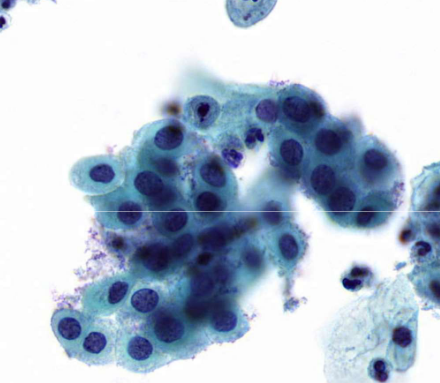

small cell carcinoma (SCLC)